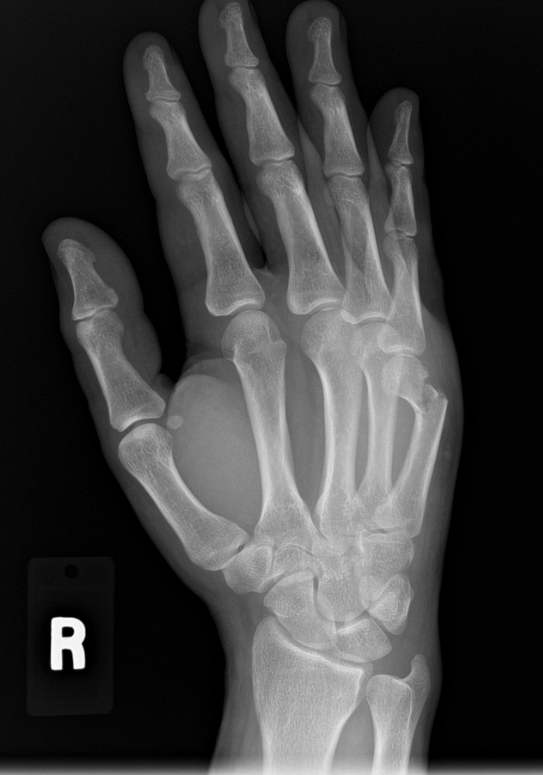

What is very common, however, is a visual loss of the knuckle and a large bump about a centimeter closer to the wrist from where the knuckle once was. This occurs when the broken bone has angled down towards the palm (see Figure 1). An x-ray will easily confirm the diagnosis, thus showing us a fracture (remember, there is no difference between the term ‘fracture’ or ‘broken bone’) through the fifth metacarpal neck.

Figure 1 - Notice the broken 5th metacarpal on the right side of the image. The ‘head’ of the bone is severely angled toward the palm. This is a ‘boxer’s fracture.’

The first of the above points is fracture angulation towards the palm. This is a measurement we take on x-ray (see Figure 2). From various studies over the years, we know that if the angulation of the fracture is less than 50 to 60 degrees, the hand can accommodate that degree of deformity.

Figure 2 - Here’s the same x-ray with an angle included. This bone is angled 64 degrees (180 degrees - 116 degrees = 64 degrees). This would be the upper limit of acceptable angulation and may be one to benefit from surgery.